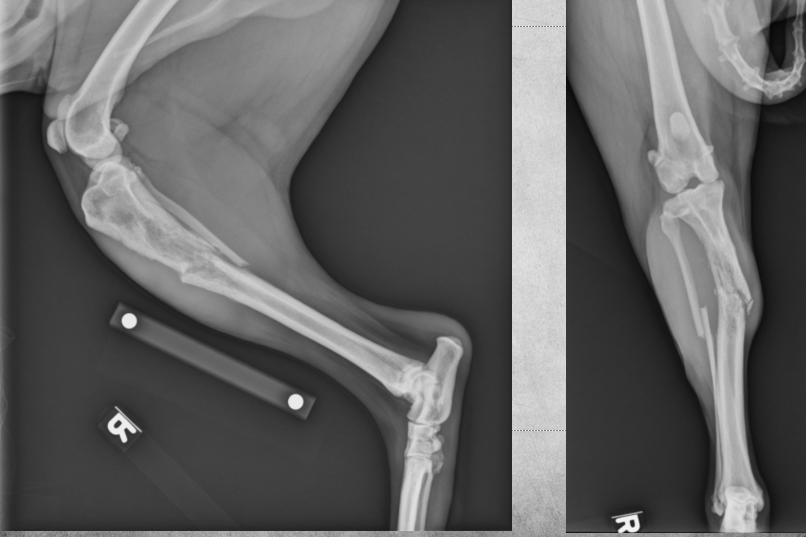

4 years old male castrated Labrador cross

Sudden and acute lamness while playing with ball

Osteolysis of the proximal third of the tibial diaphysis and very mild irregular periosteal reaction.

There is a short oblique fracture through the tibial diaphysis with several small associated fragments, mild medial and proximal displacement of the distal segment. A transverse fracture of the fibula is present at the same level.

Diagnosis: Osteosarcoma with pathologic fracture.